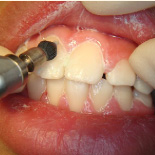

小児歯科

子供は口の中の汚れのコントロールが難しいものなので専門的な予防処置が重要。しっかり歯のあいだまで磨き込んでからフッ素を歯に塗り込んでいきます。

- 小児予防